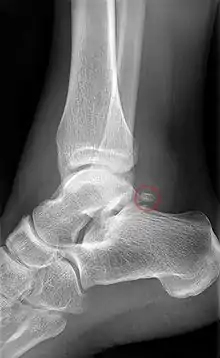

كسور

يفتقر عظم الكاحل إلى إمداد دم جيد. لهذا السبب، قد يستغرق التئام كسر عظم الكاحل وقتًا أطول من معظم العظام الأخرى. قد لا يتمكن الشخص المصاب بكسر الكاحل من المشي لعدة أشهر بدون عكازات، وسوف يرتدي جبيرة أو حذاءًا من نوع ما بعد ذلك.[7]

قد يكون من الصعب التعرف على إصابات الكاحل، وكسور العملية الجانبية على وجه الخصوص قد تكون غامضة إشعاعيًا. إذا لم يتم التعرف عليه وإدارته بشكل مناسب، فقد يؤدي كسر عظم الكاحل إلى مضاعفات طويلة الأمد.

توصلت مراجعة عام 2015 إلى إستنتاج مفاده أن كسور جسم الكاحل المعزولة قد تكون أكثر شيوعًا مما كان يعتقد سابقًا. غالبًا ما يكون لجسم الكاحل المكسور إزاحة يمكن تصورها بشكل أفضل بإستخدام التصوير المقطعي المحوسب. في حالة وجود كسر في الكاحل مصحوبًا بخلع، فإن استعادة المحاذاة المفصلية والمحورية ضرورية لتحسين وظيفة الكاحل والقدم الخلفية.[8]